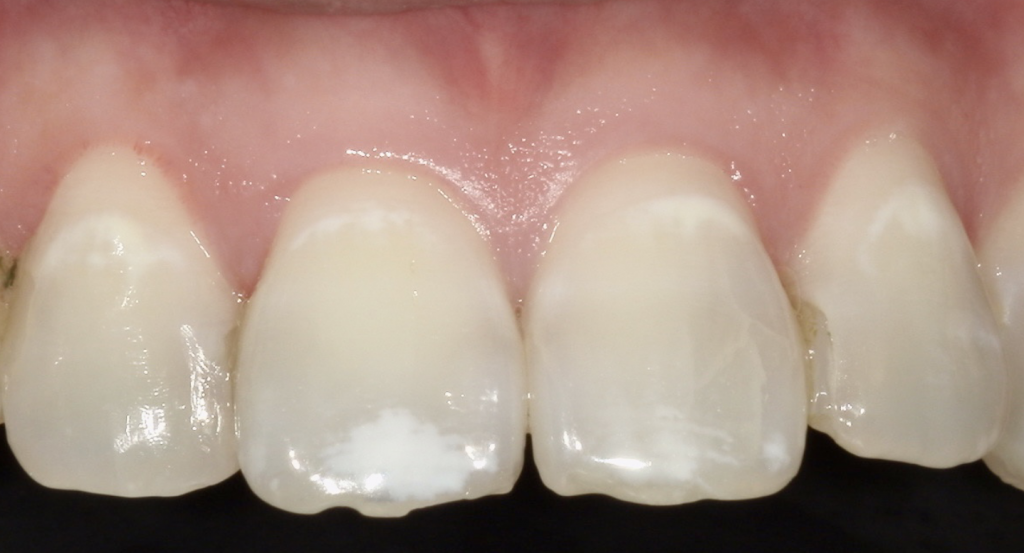

最後に、当院での治療例です♪

🔼Before

処置前に比べると、処置後白い線が薄くなっていることがわかります。